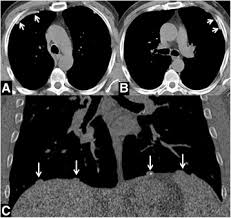

Examples Of Pleural Plaques On A A Chest Ct Arrows Indicate Pleural Download Scientific Diagram

Examples Of Pleural Plaques On A A Chest Ct Arrows Indicate Pleural Download Scientific Diagram from www.researchgate.net